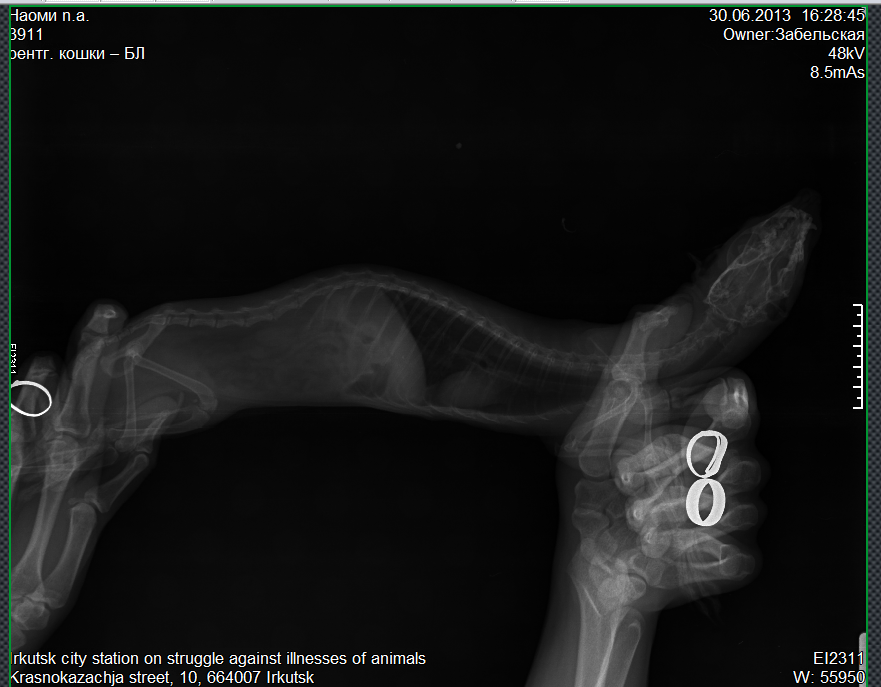

Подскажите.. у нас рахит?.... :'(

Прикрепленный файл: 6164024.png (327.7 Kb)

Feika, по снимку в такой позе - не понятно. Но, вроде судя по цвету костей (хотя это тоже от настроек аппарата и программы зависит) - рахита нет.